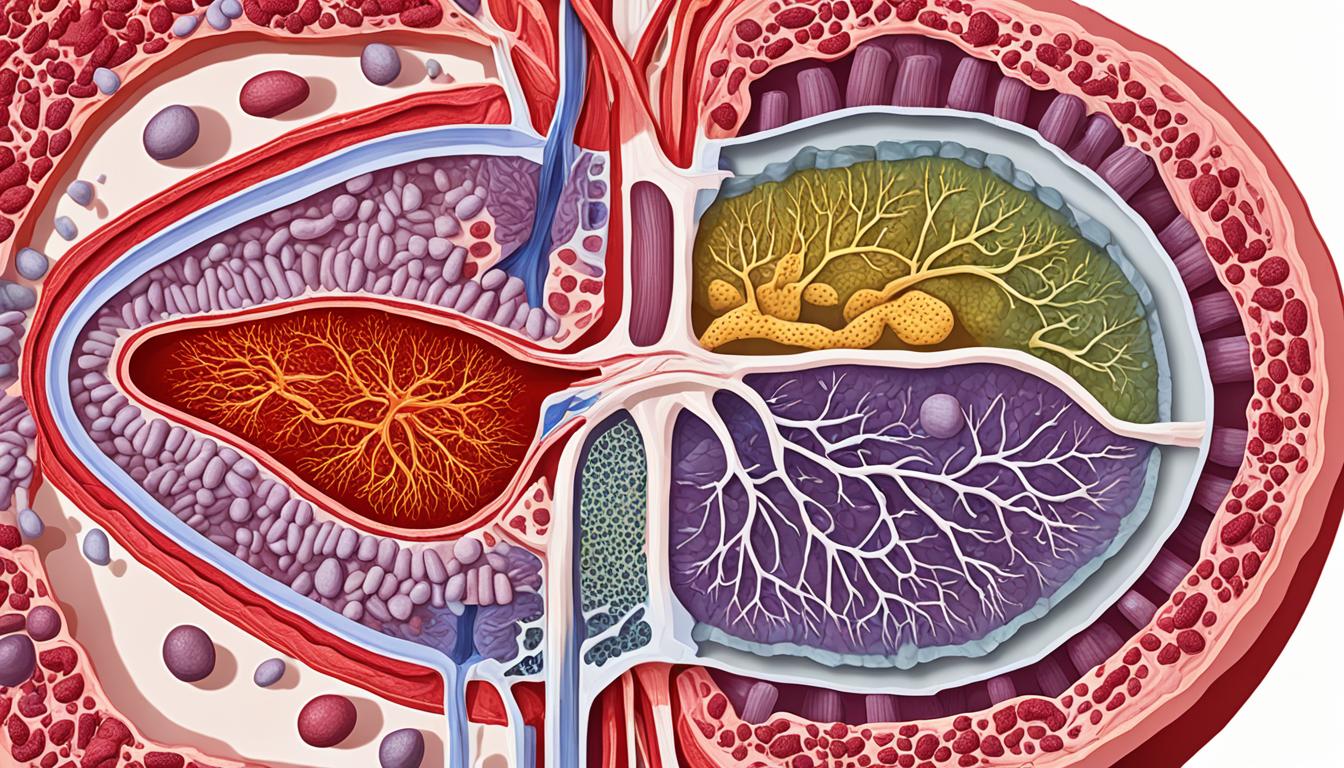

Anatomy of the Liver

The liver sits in the upper right part of your belly. It has four main lobes: left, right, caudate, and quadrate. These lobes are split into smaller parts, which is important for surgery and transplanting the liver. Knowing about these parts helps surgeons work safely and effectively.

Inside the liver lobes, there are millions of cells called hepatocytes. These cells are vital for cleaning toxins from the blood, making bile, and storing important nutrients. They can even grow back if damaged, which helps the liver heal quickly.